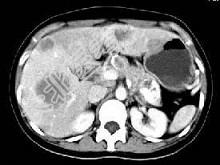

- 单项选择题根据所提供的图像,最可能的诊断为 ( )

A、胰尾囊腺癌肝转移

B、慢性胰腺炎

C、胰腺结核

D、胰岛细胞瘤

E、以上都不是